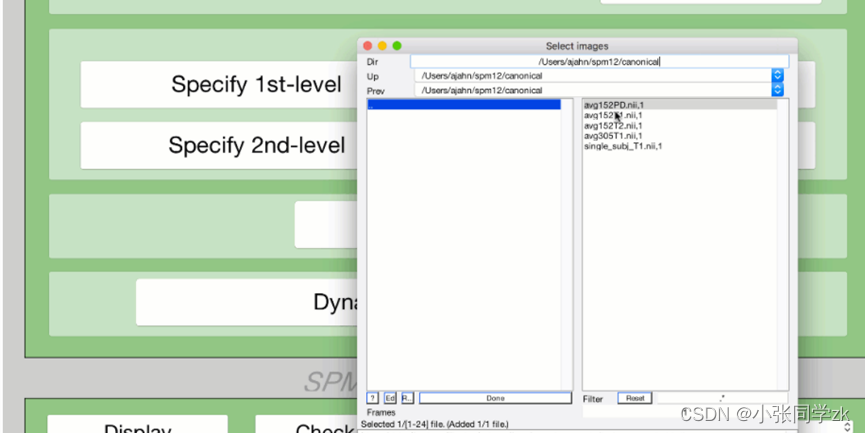

这一步完成之后,我们需要检查一下是否出错,点击Check Reg,找到w开头的功能像文件,对于第二个image,找到spm12/canonical 工作路径下的T1或者avg152T1.nii, avg305T1.nii, or single_subj_T1.nii图像,检查是否配准的好。